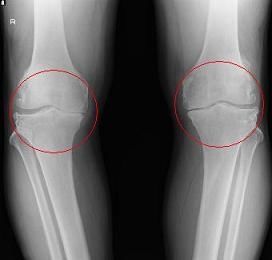

変形性膝関節症

変形性膝関節症はひざの軟骨や半月板がすりへって変形することが主な原因です。

関節が炎症を起こしたり関節液が過剰にたまることで痛みを発します。

体重の乗り方が偏るO脚やX脚はひざの痛みの大きな原因です。